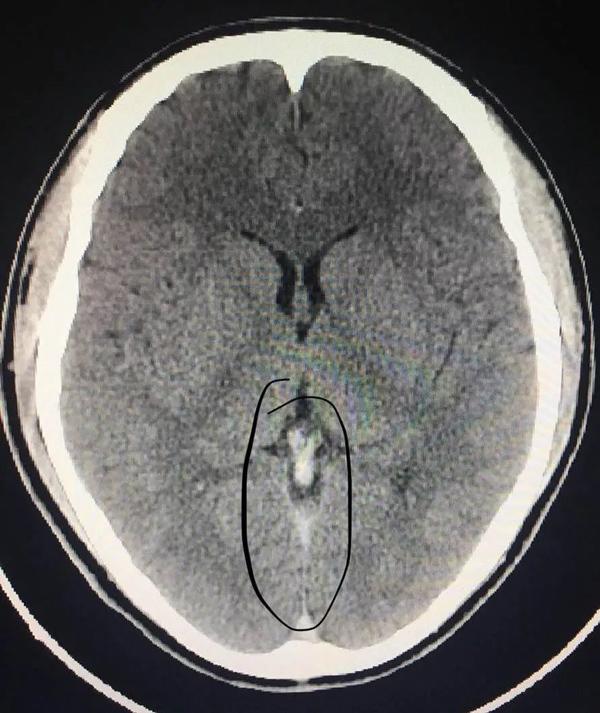

20/07/2018 16:48Nhìn phim chụp X-quang, chàng trai giật mình biết được lý do mình đau đầu không hề đơn giản

Thông qua kiểm tra CT, bác sĩ Cảnh Anh Triều làm việc tại khoa phẫu thuật thần kinh nhận định Tiêu Hà bị huyết khối tĩnh mạch xoang nội sọ.

Nếu phạm vi tắc nghẽn được mở rộng thêm có thể dẫn tới xuất huyết, đe dọa đến tính mạng. May mắn thay, nhờ đưa tới bệnh viện kịp thời nên các bác sĩ có thể nhanh chóng tiến hành điều trị, các triệu chứng buồn nôn, đau đầu cũng thuyên giảm dần.